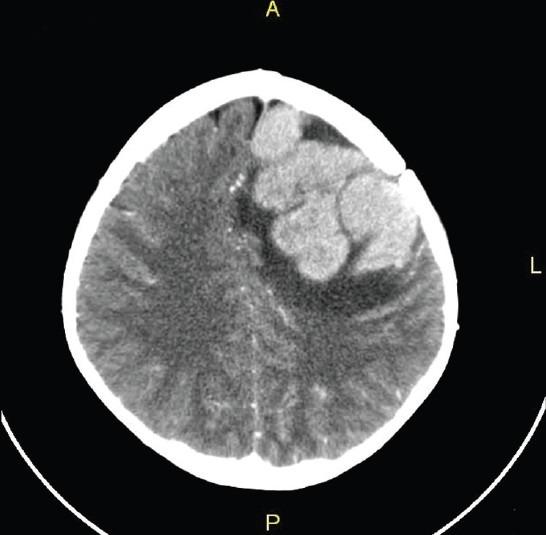

Exploración con tomografía computarizada (TC) de una recidiva tumoral en el cerebro de un niño con LLA.

Fuente: J Pediatr Neurosci. Sep-Dec 2012. doi: 10.4103/1817-1745.106482. Creative Commons 3.0.